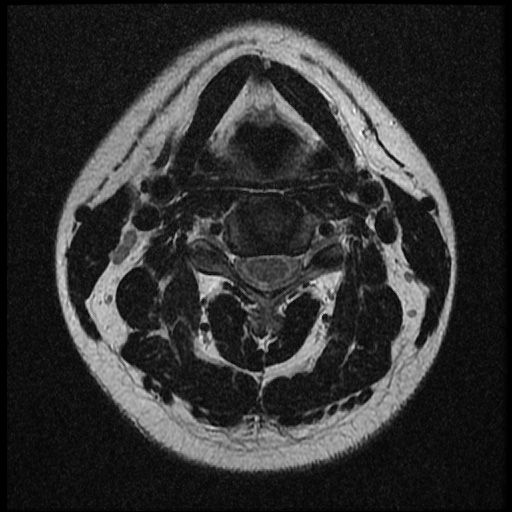

이 MRI 사진은 21년도 사고 당시 찍은 MRI 사진 입니다. 확인 부탁드립니다~

전체 mri를 다 봐여겠지만 보여주신 mri 컷에서는 의미있는 경추 디스크탈출이 보이지 않습니다.